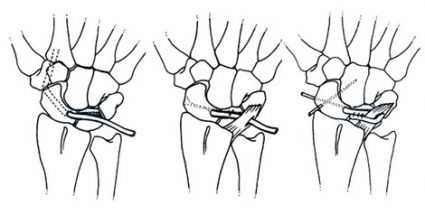

Lättreponibla felställningar utan sekundär artrosutveckling är lämpade för ligamentrekonstruktion. För den typen av skador använder vi vid handkirurgiska kliniken i Göteborg för närvarande 3LT-tekniken som har utvecklats av García-Elias och Stanley och som innebär tenodes av tre för skafolunära leden viktiga stabiliserande ligament [1]. Man utnyttjar en del av flexor carpi radialis-senan för att strama upp leden mellan scaphoideum och lunatum. Resultaten varierar och är betydligt sämre än efter en akut åtgärdad skada, varför vi ånyo starkt vill understryka vikten av en tidig diagnos.